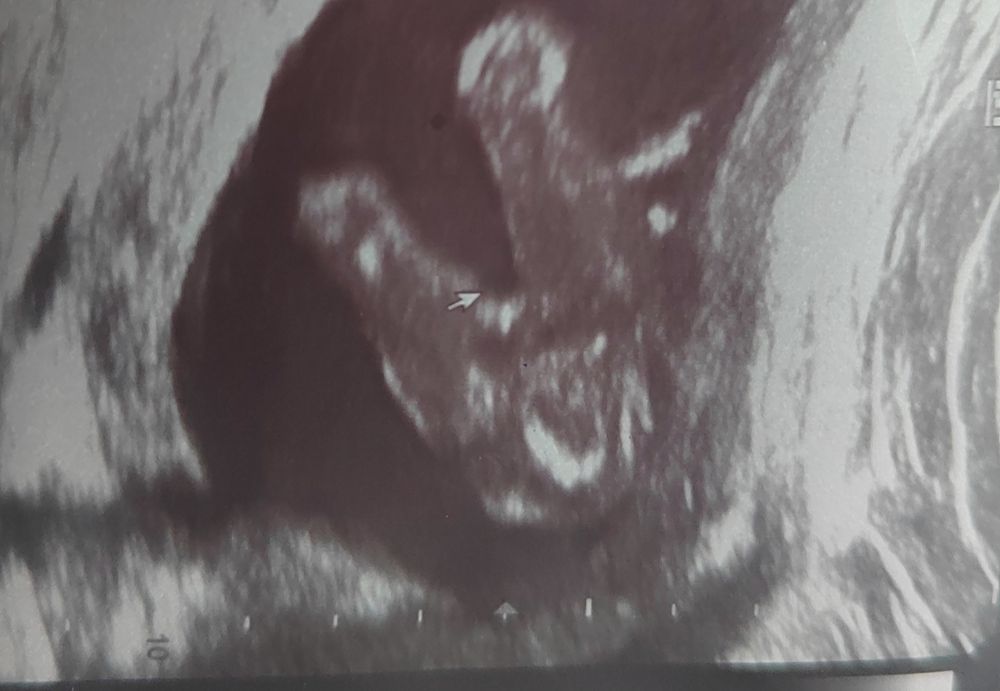

Узи плода ? 17+3 дня !

Это девочка )

Если интересует пол - похоже на девочку)

Таро Расклады, у мальчика на таком сроке все причиндалы прекрасно видно